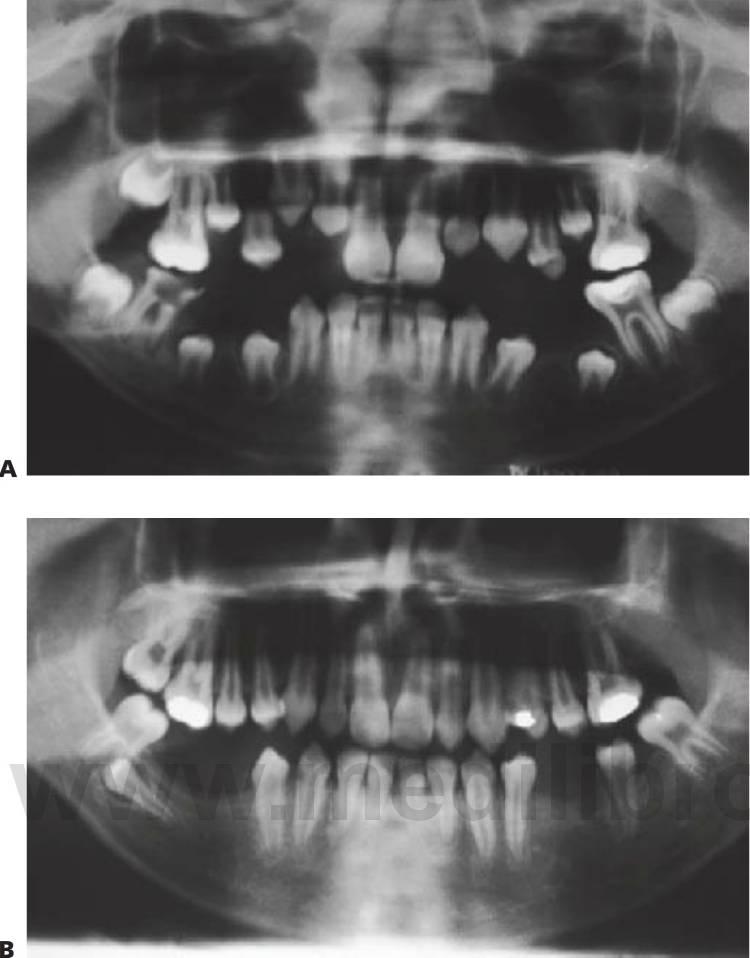

Displasia cleidocraneal (OMIM 119600)

Este trastorno se hereda con un rasgo autosómico dominante y se caracteriza por una frecuencia elevada de mutaciones espontáneas. Se ha localizado en 6p21 con mutaciones en el gen CBFA1 (fig. 9.9).

- Múltiples dientes supernumerarios (fig. 9.9A).

- Retraso en la erupción de los dientes.

- Formación de quistes dentígeros.

Debe observarse que la extracción de la dentición temporal sin exposición quirúrgica de los dientes permanentes no permite la erupción de estos últimos, por lo que se requiere una intervención en dos tiempos. En la primera operación se exponen los segmentos anteriores y se extraen los segmentos anteriores temporales y todos los dientes supernumerarios que pueda haber. Se exponen quirúrgicamente los dientes permanentes, ya sea mediante colgajos reposicionados apicalmente o mediante cadenas de oro cementadas para la tracción ortodóncica.

A continuación, los dientes anteriores se alinean ortodóncicamente. En la segunda operación se extraen los molares temporales, se extraen quirúrgicamente los dientes supernumerarios restantes y se exponen los premolares y molares en los segmentos bucales. Posteriormente se procede al tratamiento ortodóncico definitivo y puede requerirse la realización de una cirugía ortognática en los casos de maloclusión de clase III esquelética grave. Resulta evidente que el tratamiento es muy prolongado en el tiempo y el odontólogo debe valorar los problemas potenciales relacionados con el cumplimiento del tratamiento por parte del niño.